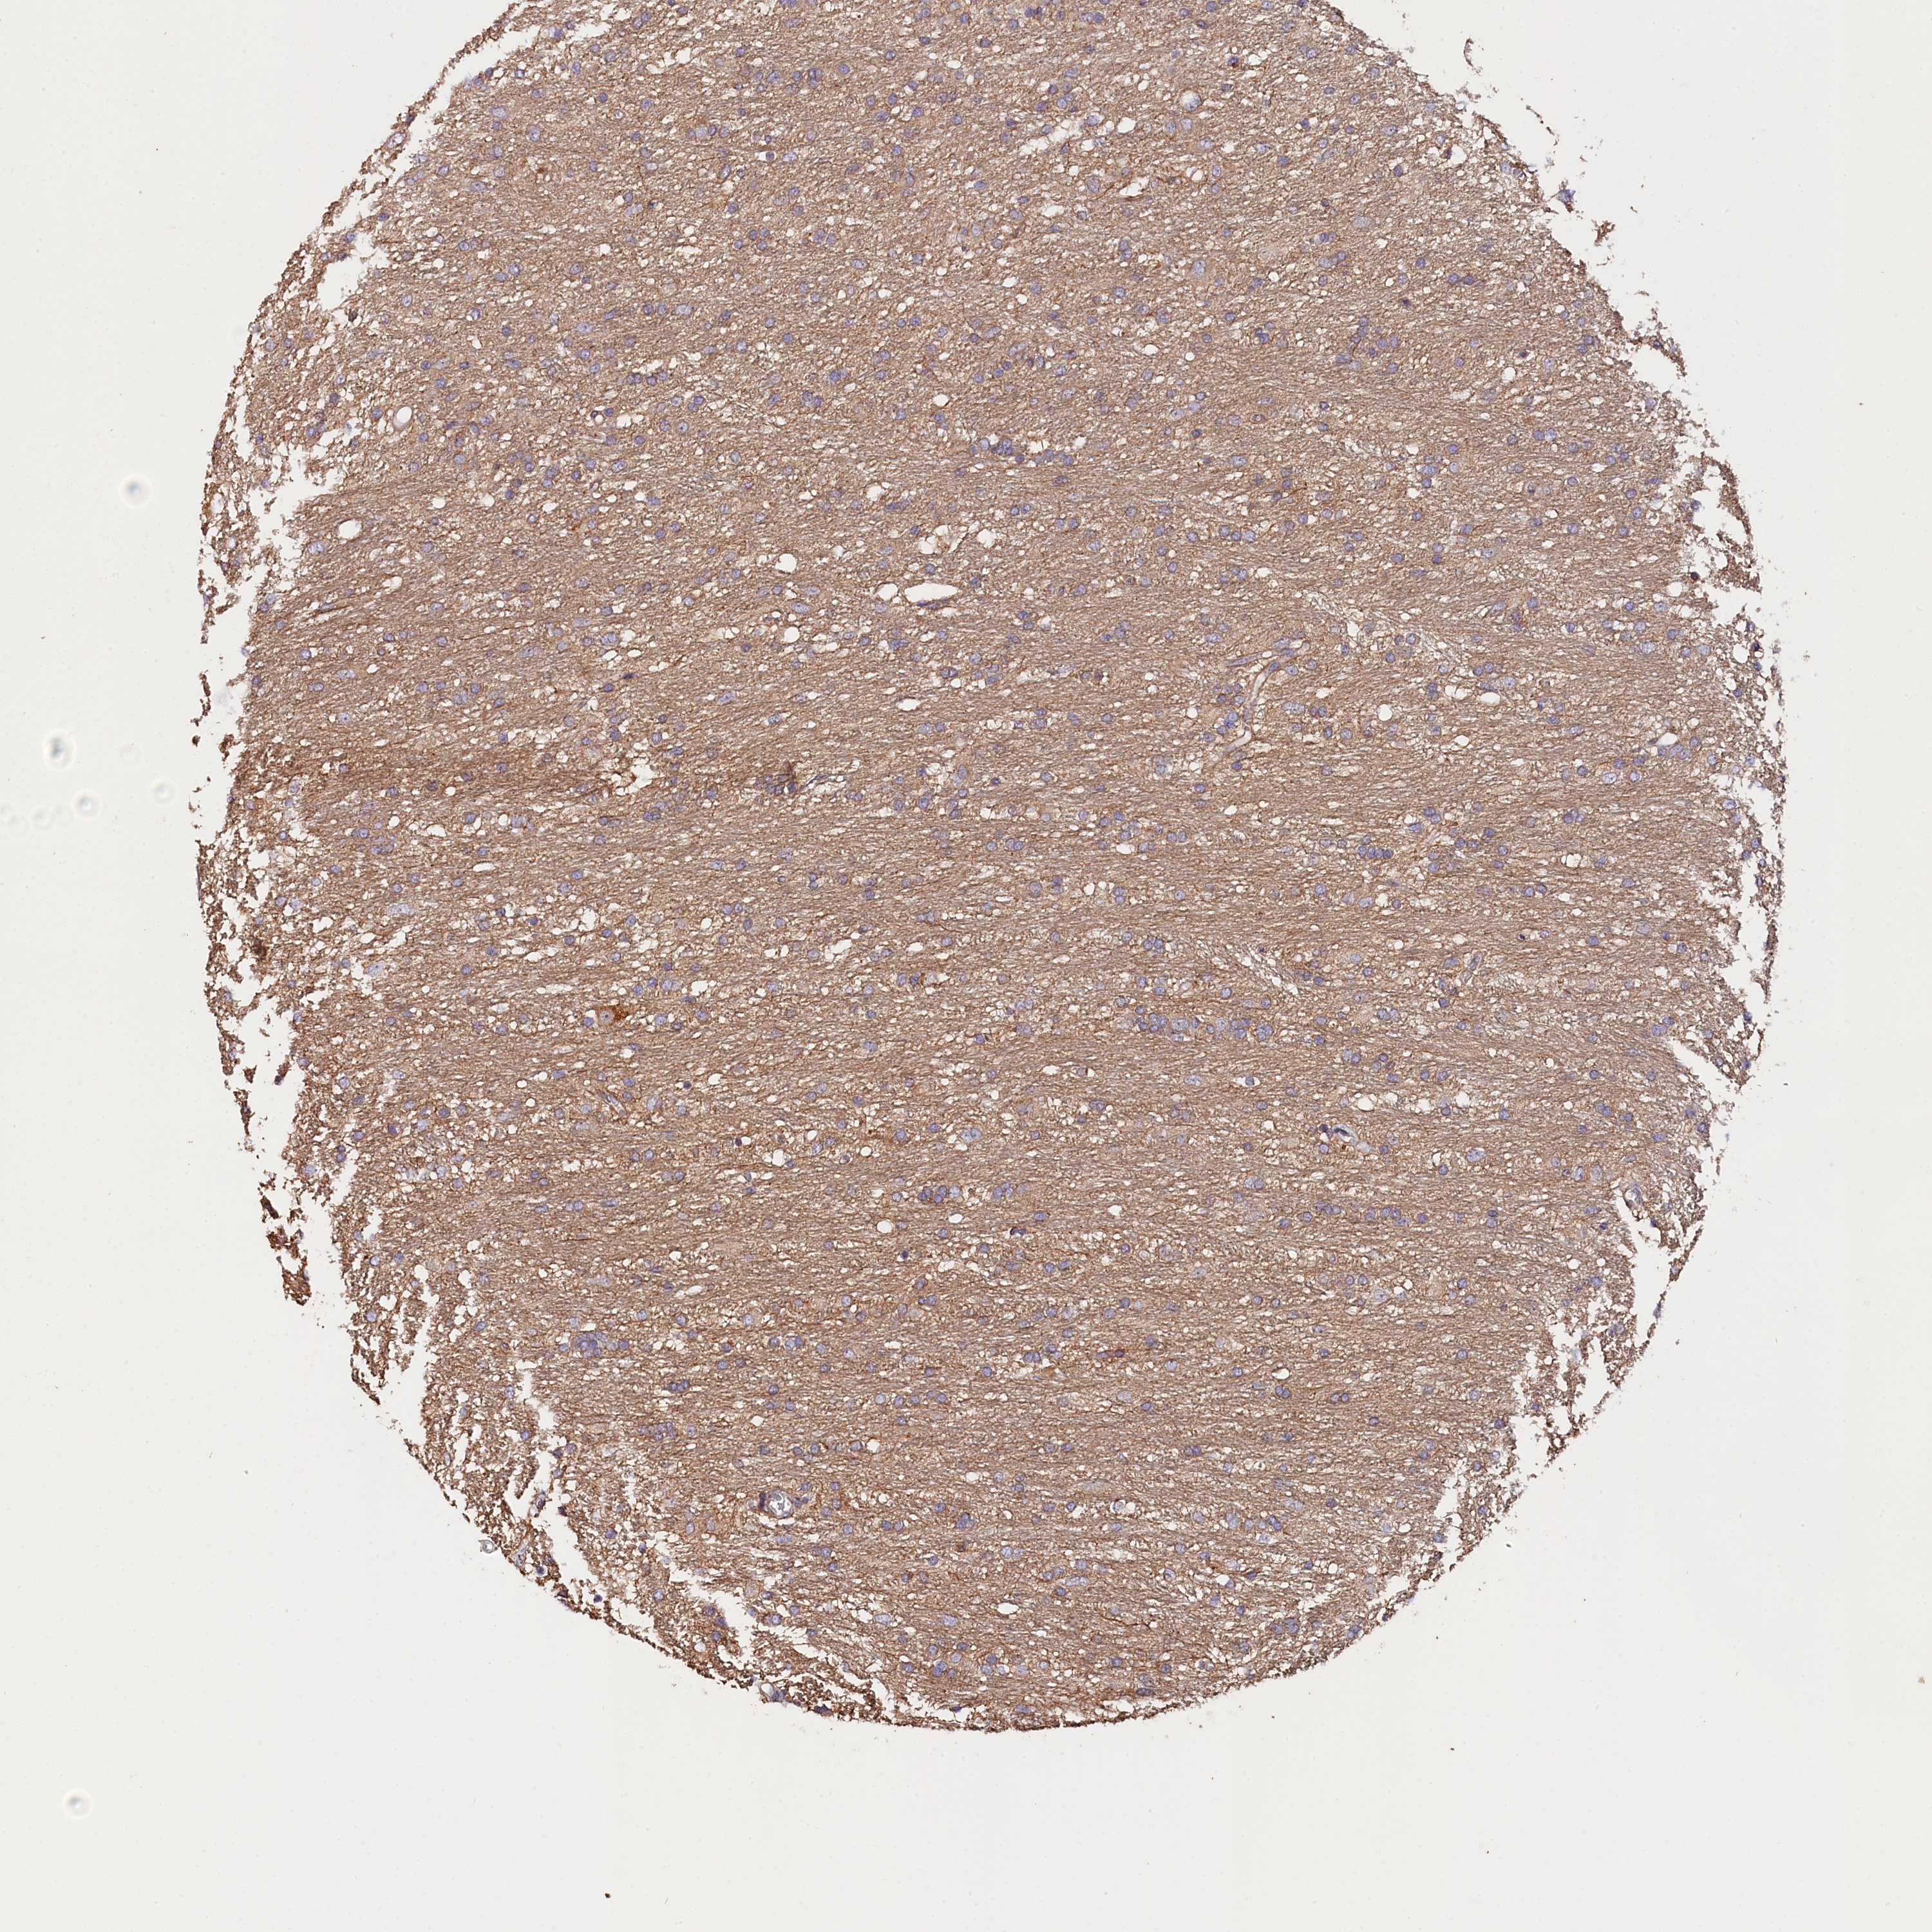

GLIOMA - Protein expressioni

A mouse-over function shows sample information and annotation data. Click on an image to view it in a full screen mode. Samples can be filtered based on level of antibody staining by selecting one or several of the following categories: high, medium, low and not detected. The assay and annotation is described here.

Note that samples used for immunohistochemistry by the Human Protein Atlas do not correspond to samples in the TCGA dataset.

Antibody stainingi

Antibody staining in the annotated cell types in the current human tissue is reported as not detected, low, medium, or high, based on conventional immunohistochemistry profiling in selected tissues. This score is based on the combination of the staining intensity and fraction of stained cells.

Each image is clickable and will lead to virtual microscopy that enables deeper exploration of all samples and also displays staining intensity scores, fraction scores and subcellular localization as well as patient and tissue information for each sample.

Antibody HPA041165

Antibody HPA041839

Staining

High

Medium

Low

Not detected

Intensity

Strong

Moderate

Weak

Negative

Quantity

>75%

75%-25%

<25%

None

Location

Nuclear

Cytoplasmic/membranous

Cytoplasmic/membranous,nuclear

Glioma, malignant, High grade

Glioma, malignant, Low grade